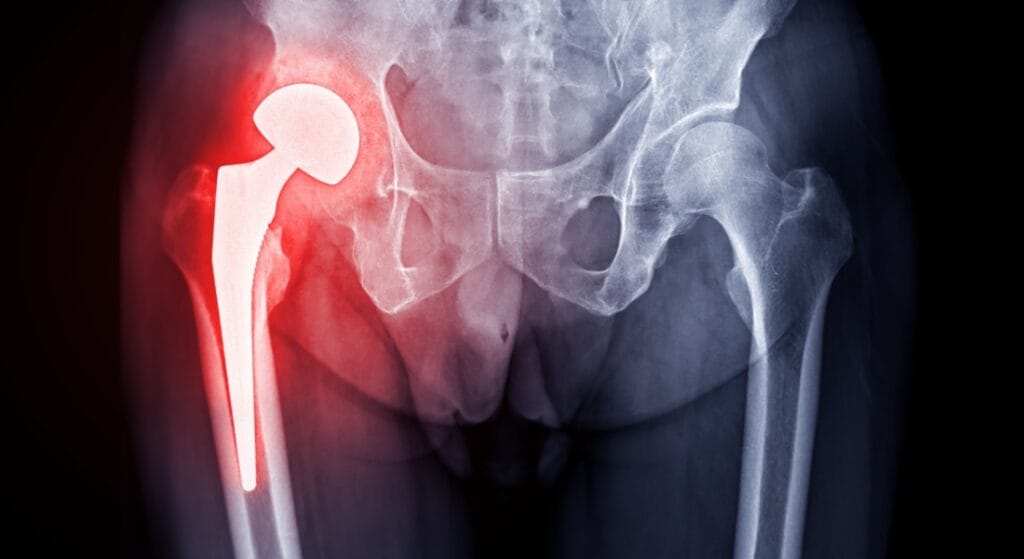

Đau khớp háng bên phải là cảm giác đau xuất hiện tại vùng khớp háng phải – nơi nối giữa xương đùi và khung chậu. Cơn đau có thể khu trú ở vùng bẹn phải, mông phải, mặt ngoài hoặc mặt trước đùi, đôi khi lan xuống gối. Mức độ đau thay đổi từ âm ỉ, khó chịu đến đau nhói, dữ dội, xuất hiện khi vận động hoặc thậm chí cả lúc nghỉ ngơi.

- Hoại tử chỏm xương đùi là bệnh lý nguy hiểm, tiến triển âm thầm. Người bệnh thường đau sâu trong háng, đau tăng dần theo thời gian và có thể đau cả khi nghỉ. Các yếu tố nguy cơ bao gồm lạm dụng rượu bia, dùng corticoid kéo dài, chấn thương hoặc bệnh lý chuyển hóa.

Không phải tất cả các trường hợp đau khớp háng bên phải đều nguy hiểm. Nếu nguyên nhân là quá tải, sai tư thế hoặc vận động mạnh, cơn đau có thể tự cải thiện sau khi nghỉ ngơi, điều chỉnh thói quen. Tuy nhiên, với các bệnh lý như thoái hóa, viêm khớp, hoại tử chỏm xương đùi hoặc chấn thương nặng, nếu không được điều trị sớm, bệnh có thể tiến triển nặng dẫn đến biến chứng như mất vận động, teo cơ, biến dạng khớp hoặc thậm chí tàn phế.

- Can thiệp chuyên sâu: Khi điều trị bảo tồn không hiệu quả hoặc tổn thương nặng, bác sĩ có thể chỉ định tiêm khớp hoặc phẫu thuật nhằm khôi phục chức năng và giảm đau cho người bệnh.